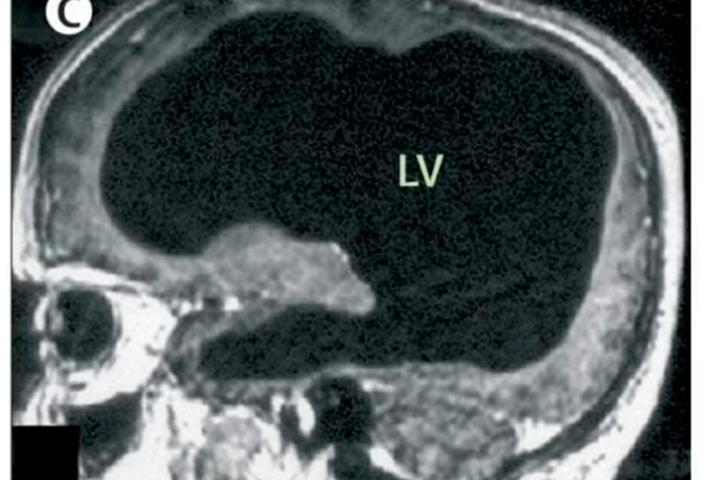

Homem descobre aos 44 anos que vive com cérebro oco Internacional

Homem descobre aos 44 anos que vive com cérebro oco